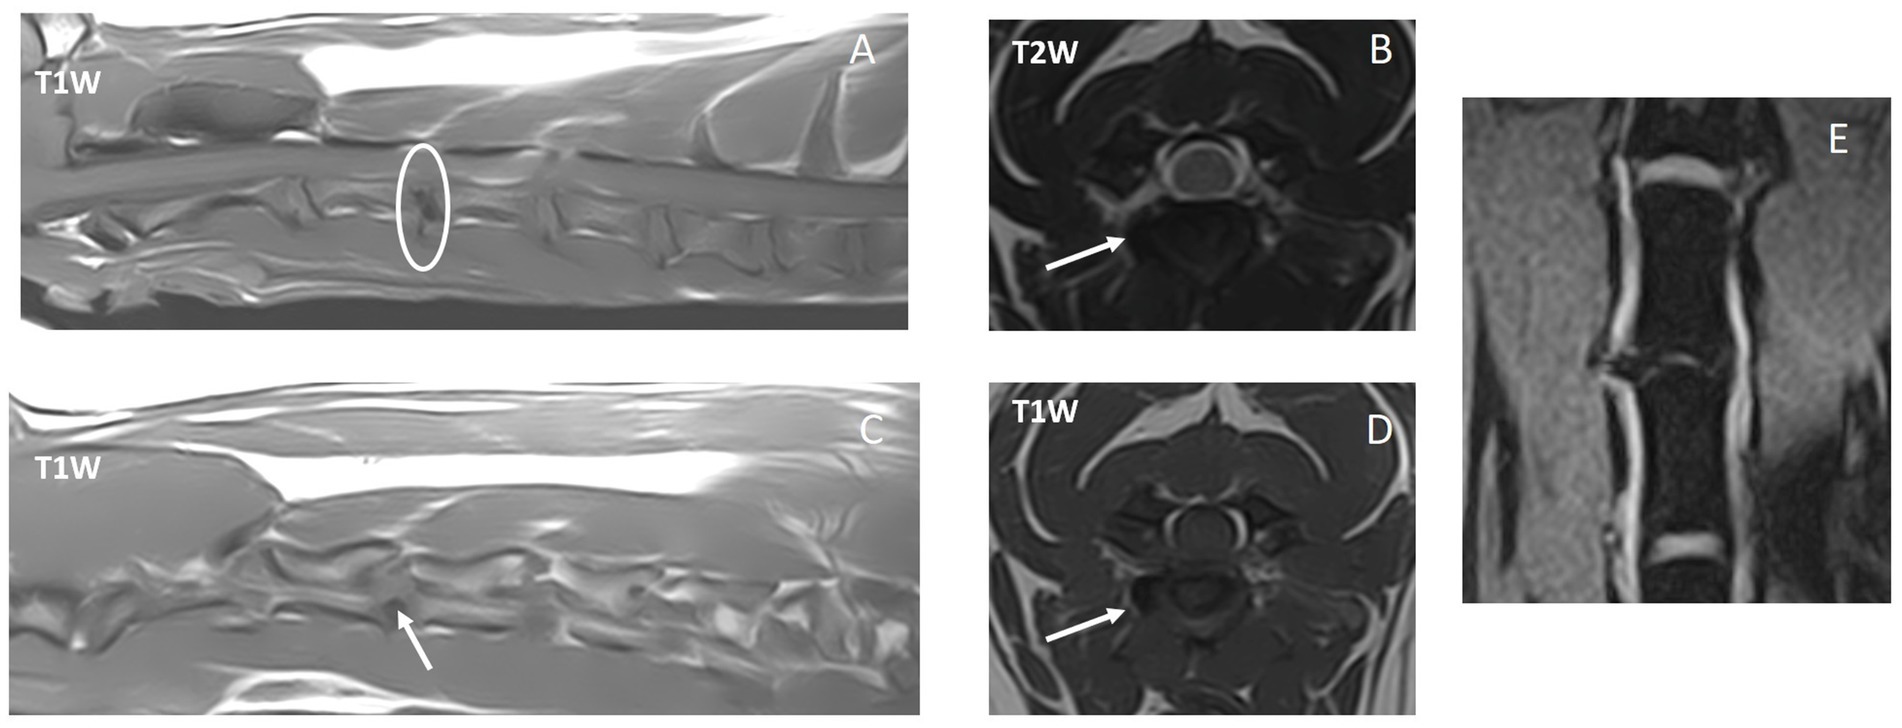

En la Tabla 2 se incluye un resumen de las modalidades de diagnóstico por imagen empleadas y los hallazgos. Las IVDE cervicales laterales lejanas se diagnosticaron con resonancia magnética de alto campo en 6/10 (60%) perros (ejemplos en las figuras 2, 3), mielograma por TC en 2/10 (20%) perros (ejemplo en la figura 4) y TC y resonancia magnética de campo bajo en 2/10 (20%) perros. Un perro (1/10, 10%) tenía un IVDE lateral lejano (C2-3, izquierda) y un IVDE lateral lejano/foraminal (C3-4, izquierda). Por lo tanto, informamos las características de 11 IVDE. Se diagnosticó IVDE lateral lejano en todos los perros (10/10, 100%); 6/11 (55%) fueron IVDE foraminales/laterales lejanos. La lateralización fue hacia la izquierda en 7/11 (64%) y hacia la derecha en 4/11 (36%) IVDEs. Todas las extrusiones laterales lejanas y la combinación de extrusiones laterales/foraminales se encontraban al nivel de un espacio IVD reducido en comparación con los espacios IVD adyacentes, y IVD parcialmente mineralizado (hiperatenuante en la TC, marcadamente hipointenso en todas las secuencias en la RM). Los espacios IVD afectados fueron: C3-4 (6/11, 55%), C5-6 (3/11, 27%) y C2-3 (2/11, 18%). A partir de las imágenes de TC, todas las extrusiones foraminales y laterales lejanas eran homogéneas y mineralizadas (hiperatenuantes a la médula espinal, HU > 500). A partir de las imágenes de resonancia magnética, las lesiones extradurales eran ligeramente heterogéneas, pero predominante y marcadamente hipointensas en todas las secuencias, compatibles con mineralización. Al comparar entre las secuencias de resonancia magnética, el material extradural fue T2W y T1W isointenso al hueso cortical, y esto resultó en una disminución de la visibilidad en las imágenes T2W en comparación con las imágenes T1W y T2*W (Figuras 1, 2). En todos los casos, la lesión extradural causó efecto de masa y la consiguiente falta de visualización de la arteria vertebral y el nervio espinal a lo largo de la longitud donde se localizó el material extradural. A partir de las imágenes de resonancia magnética, las secuencias de supresión de grasa (la mayoría de ellas STIR dorsal) revelaron una hiperintensidad leve y mal definida de los músculos epaxiales y los tejidos perineurales alrededor del material extruido. La lateralización de los signos clínicos coincidió con la lateralización de la IVDE lateral lejana (en las imágenes) en todos los casos en los que se observó lateralización.

Ejemplo de caso: caso #8

Una perra de 8 años castrada de 9 kg de raza (con un fenotipo condrodistrófico) se presentó con una historia de 2 semanas de hiperestesia cervical episódica recurrente de inicio agudo, vocalización («ataques de dolor» o episodios de aullidos) y cojera de las extremidades torácicas derechas / firma de la raíz nerviosa. Sobre la base de la sospecha de convulsiones epilépticas, el veterinario de referencia había prescrito al perro fenobarbital 2 mg/kg cada 12 h sin resolución de los signos clínicos. El propietario había hecho algunos videos de los ataques y el período posterior a un ataque en su casa (Videos complementarios S2 y S3). Estos mostraron a un perro subjetivamente consciente, con una postura cautelosa, firma de raíz nerviosa y vocalización aguda (aullidos) de 30 s a 2 min de duración. Después del episodio, el perro estaría subjetivamente letárgico, exhibía una firma de raíz nerviosa de la extremidad torácica derecha y frecuentemente se lamía la nariz. Esto fue interpretado como signos post-ictales por el veterinario de referencia. El examen clínico general no presentaba presentaciones. El examen neurológico mostró hiperestesia cervical, principalmente cuando el cuello estaba flexionado hacia la izquierda y se realizó una palpación profunda sobre la zona cervical media derecha, dorsal a la tráquea y ventral a la musculatura extensora del cuello. Después de la palpación profunda, las fasciculaciones eran palpables superficialmente en la musculatura cervical lateral derecha. El perro dudó en sacudir la cabeza y solo la movió ligeramente en la prueba de la oreja. Hubo ataxia propioceptiva general leve de las extremidades pélvicas atribuida al uso de fenobarbital. Por lo demás, el examen neurológico estaba dentro de los límites normales. La resonancia magnética de alto campo reveló una IVDE lateral derecha C3-4 (Figura 3). Se inició tratamiento médico con carprofeno (2 mg/kg cada 12 h durante 2 semanas) y gabapentina (11 mg/kg cada 8 h durante 12 semanas). Se añadió amitriptilina (1,1 mg/kg cada 12 h) debido a episodios recurrentes de dolor después de una semana. Este tratamiento fue eficaz y se redujo lentamente durante los siguientes 2 meses (primero carprofeno, luego gabapentina, luego amitriptilina). Se observó una recurrencia de los signos de dolor a los 9 meses de la primera presentación (en remisión durante los 7 meses anteriores) y se trató con meloxicam y gabapentina solo durante 2 y 4 semanas, respectivamente. En ese momento no se realizaron más pruebas diagnósticas. No se informaron signos de dolor a partir de entonces, con un seguimiento a largo plazo de 18 meses después de la primera presentación.

En nuestro estudio, 10 perros tenían 11 IVDEs: 6/11 eran IVDE combinados far-lateral/foraminal y 5/11 eran IVDE pura far-lateral (es decir, el material extruido se localizaba distal al foramen, lateral al IVD). Las IVD laterales lejanas en perros se han descrito con mayor frecuencia en la zona toracolumbar, afectando principalmente a las IVD lumbares caudales (L5-6 y L6-7) (7). La falta de publicaciones sobre las IVED cervicales en extremo sugiere que rara vez se diagnostica. El conocimiento de este tipo de IVDE sigue siendo de vital importancia para los clínicos, especialmente para aquellos que realizan e interpretan estudios de diagnóstico por imagen. Todas las extrusiones de disco foraminal/far-distal incluidas en este estudio estaban mineralizadas y estaban al nivel de un espacio de disco intervertebral estrecho con un disco intervertebral parcialmente mineralizado. Dado que las lesiones mineralizadas y las estructuras óseas se evalúan bien a partir de las imágenes de TC, estas lesiones eran obvias y se diagnosticaban fácilmente mediante TC. La mineralización puede ser más difícil de describir a partir de estudios de resonancia magnética y, por lo tanto, cuando se sospecha una extrusión de disco foraminal/distal lejano, es importante incluir varias secuencias y varios planos.

• Incluir T2W sagital y T1W sagital para visualizar un disco mineralizado intervertebral estrechado (hipointenso en T2W e hipointenso en T1W).

• Secuencias de supresión de grasa dorsal (como STIR, DIXON), con el fin de evaluar cualquier intensidad de señal anormal lateralizada de los tejidos paravertebrales y perineurales.

• T2W, T1W y T2* transversales a nivel de los forámenes sospechosos/extrusión distal lejana desde el nivel del cuerpo medio de la vértebra craneal hasta el cuerpo medio de la vértebra caudal con respecto al espacio de interés IVD. Un IVD de interés puede definirse como cualquier IVD que muestre características de señal consistentes con la degeneración (p. ej., T2-hipointensidad del núcleo pulposo). La combinación de estas tres secuencias ayudará a visualizar con precisión el material del disco extruido y corroborar la mineralización (hipointensa en todas las secuencias, mejor representada en T2*). Estos planos transversales permitirán la evaluación de los nervios espinales y las arterias vertebrales.

• Seleccione el grosor de corte adecuado, idealmente 2,5 mm cuando utilice las secuencias anteriores.

• Se pueden agregar imágenes PROSET (excitación de agua) para evaluar más a fondo los nervios espinales y evaluar su tamaño y curso.